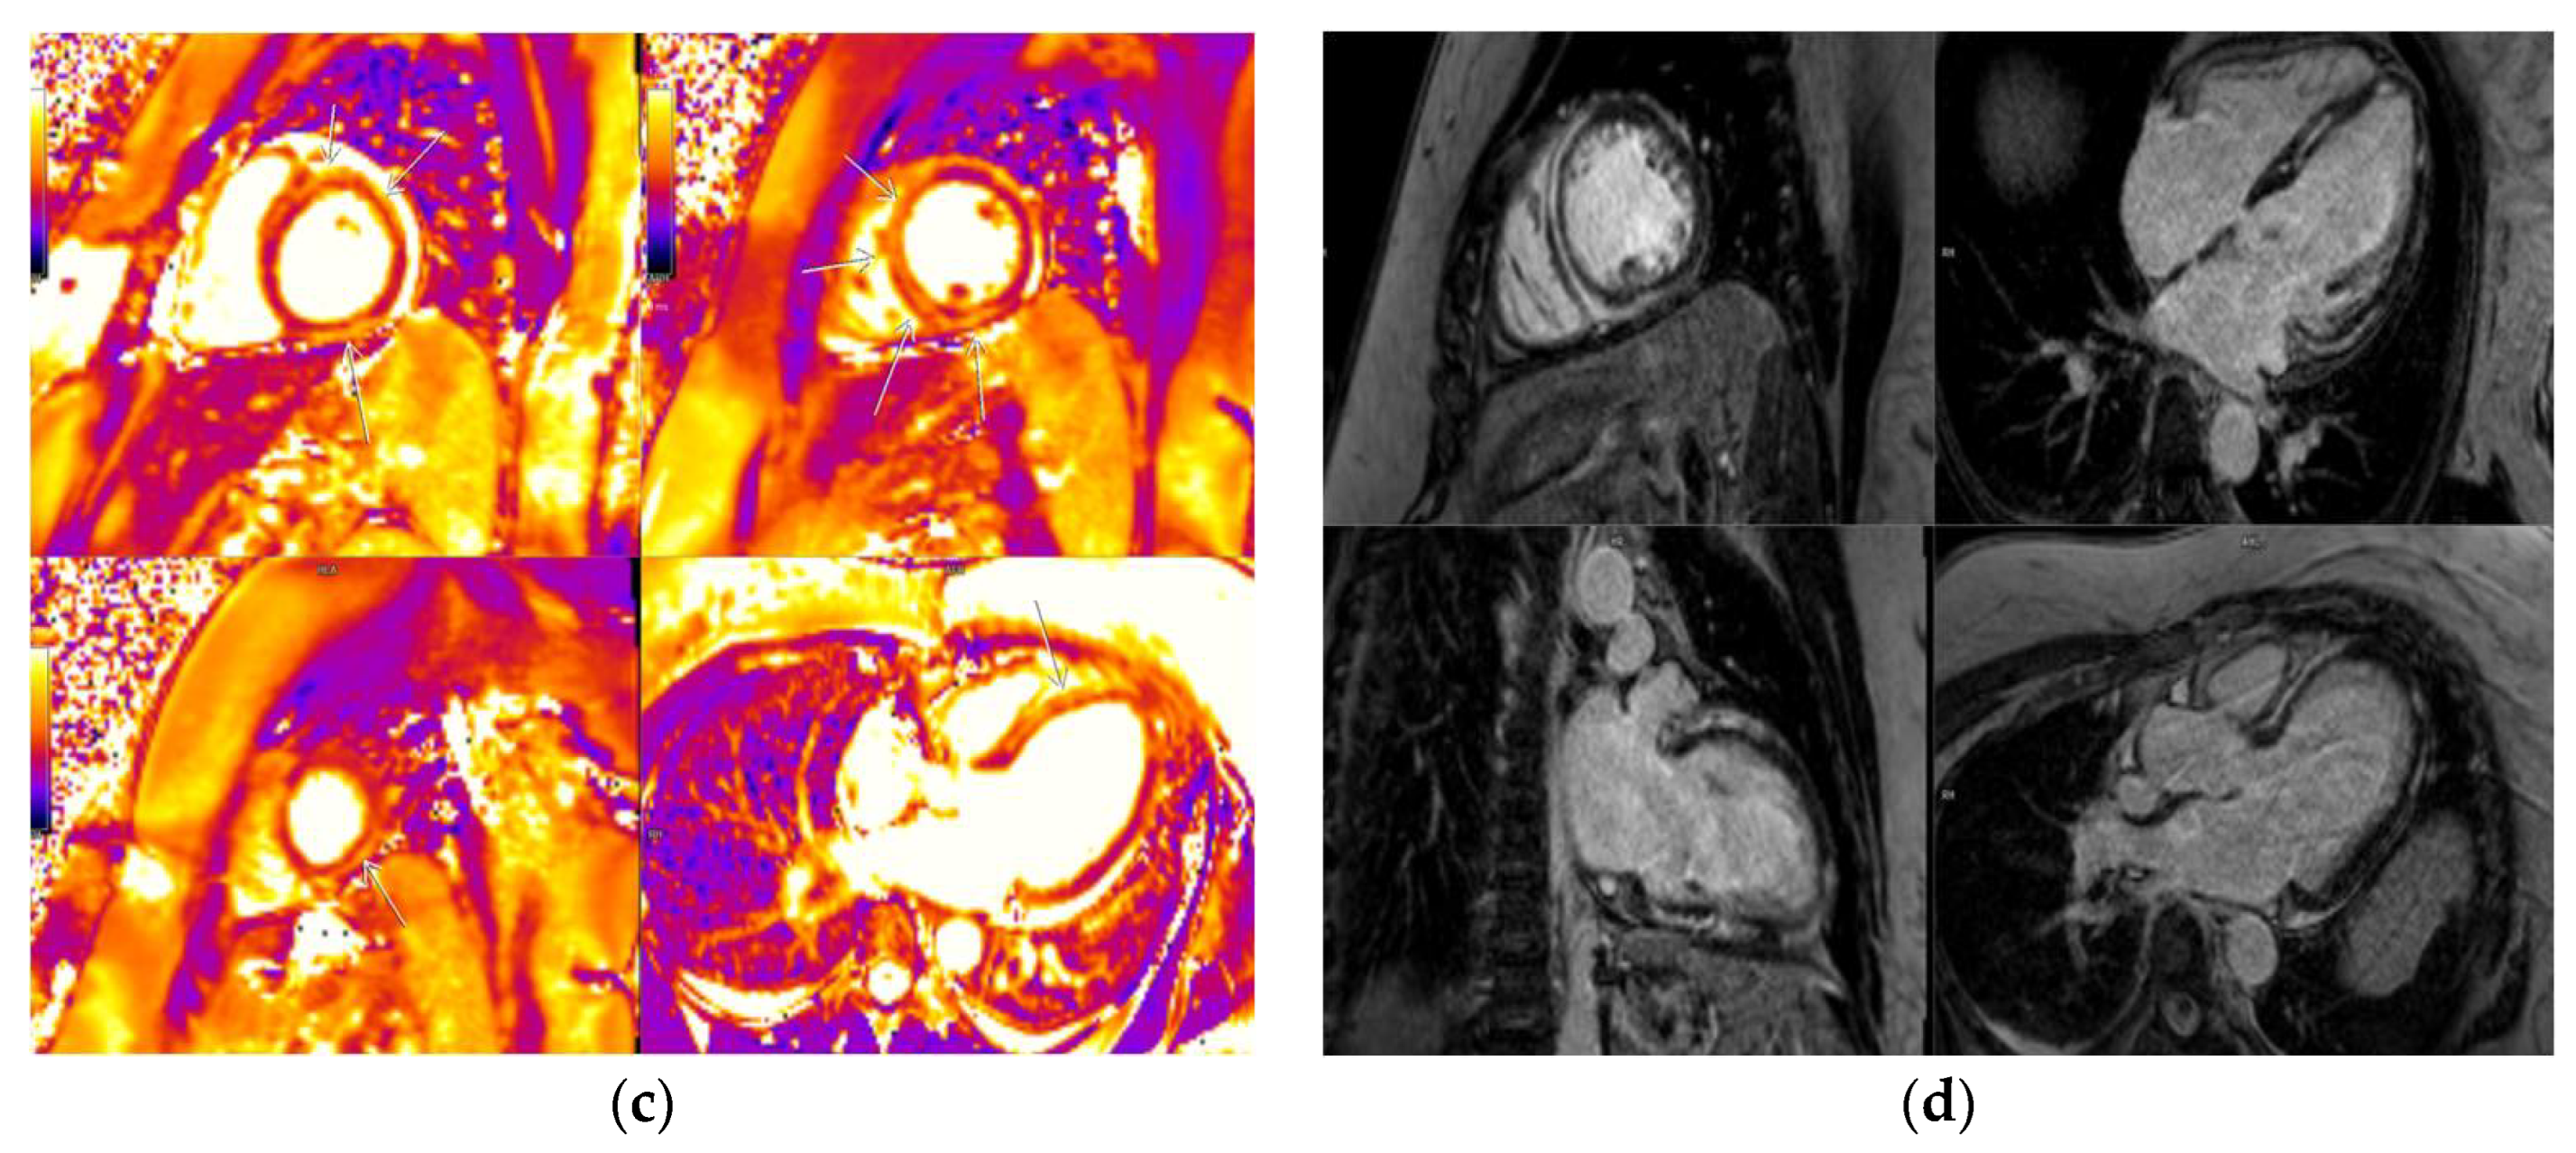

3.2. CMR Findings

3.5. LGE Localization